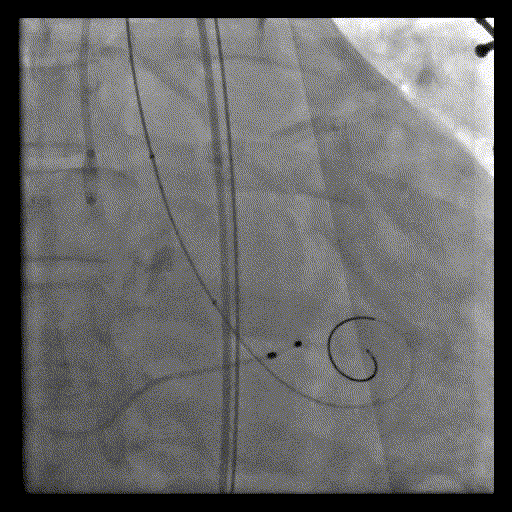

输送系统过弓及跨瓣

初始释放位置造影